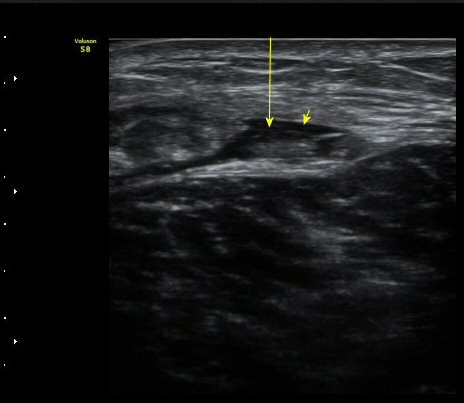

ÃÊÀ½ÆÄ °Ë»ç

¼ö»ó ÈÄ 2ÀÏ Â°

³»Ãø ºñº¹±Ù Á¾´Ü¸é°Ë»ç¿¡¼­ ±ÙÀ°°ú ÈûÁÙ ÀÌÇà ºÎÀ§¿¡ ÀÛÀº ÆÄ¿­°ú ¼ö¾× Àú·ù, ÆÄ¿­ µÈ

±ÙÀ°ÀÇ ±ÙÀ§ºÎ·Î ´ç°ÜÁüÀÌ °üÂû µÊ(±×¸² 1, 2, 3).